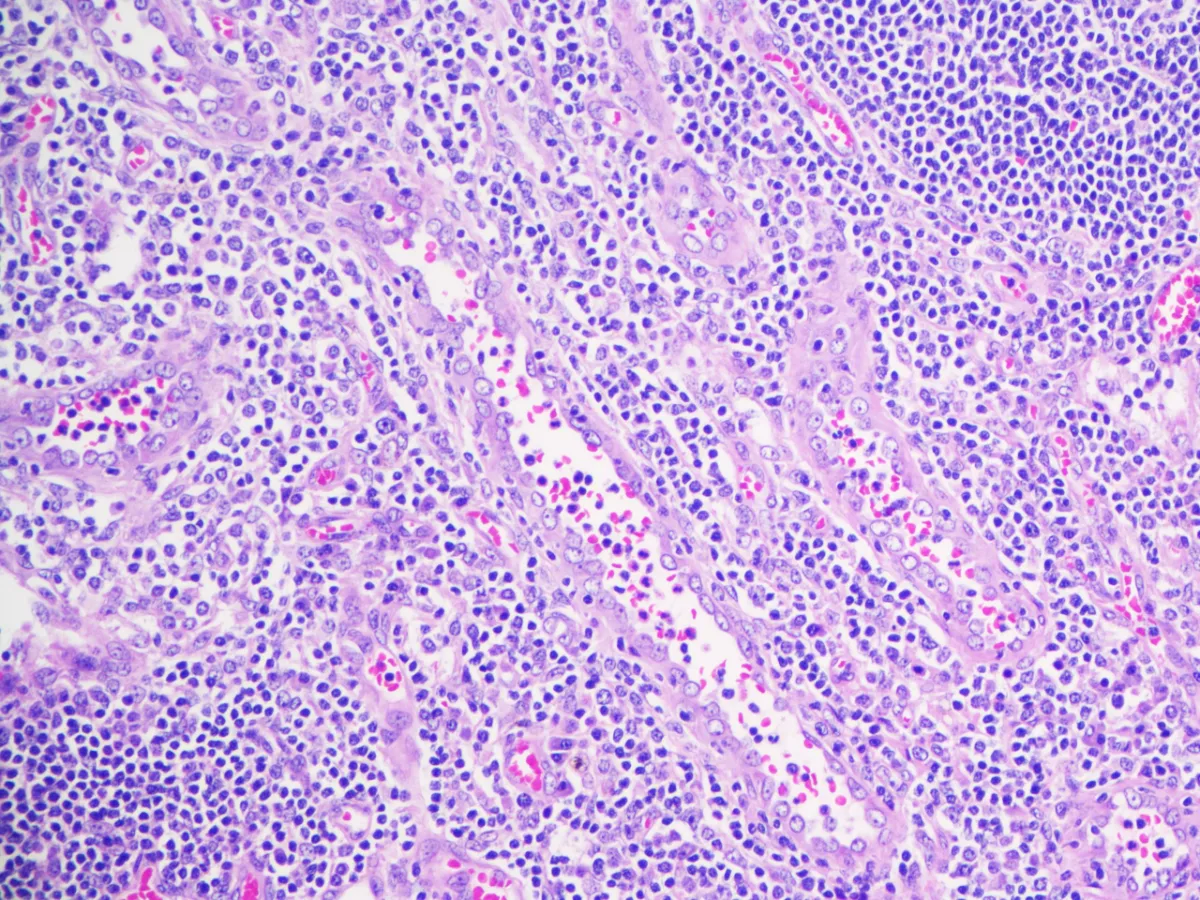

Diagnóstico: Enfermedad de Castleman, variante hialino-vascular.

- La variante hialino-vascular es la más frecuente en la EC unicéntrica, y se caracteriza por una hiperplasia linfoide con centros germinales regresivos y zona del manto expandida en aspecto “en capas de cebolla”. Se acompaña de proliferación vascular en forma de vénulas con endotelio alto, y células dendríticas foliculares prominentes (PMID: 35997567).

- En el estudio citológico de la EC se observa proliferación de vasos asociados a centros germinales (PMID: 18855889).